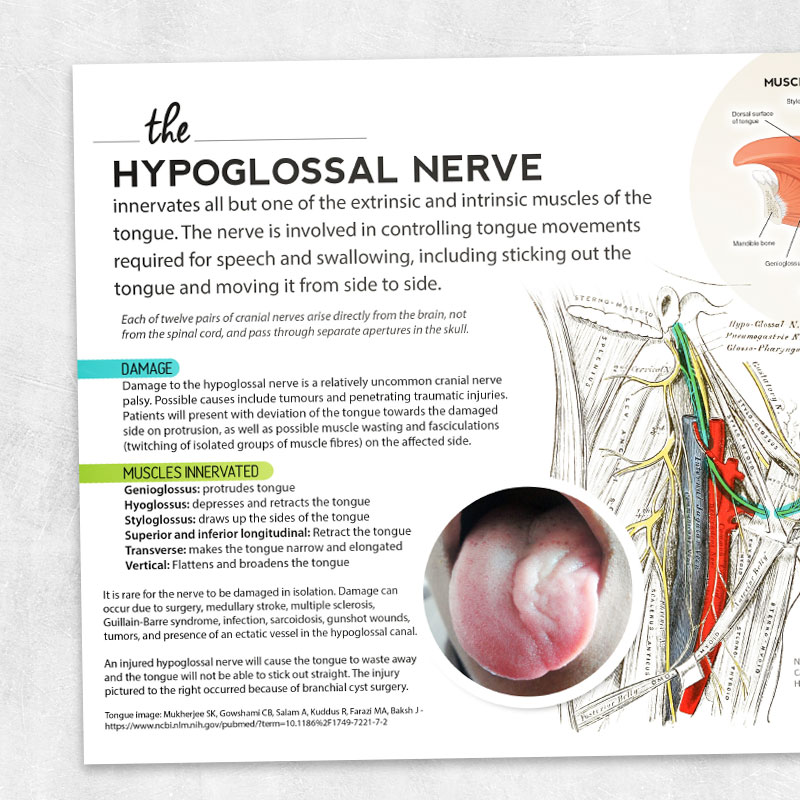

The Hypoglossal Nerve – Printable handouts for speech, occupational …

The Hypoglossal Nerve (CN XII) | Geeky Medics

Persistent Idiopathic Isolated Hypoglossal Nerve Palsy – Practical …

Hypoglossal Nerve Palsy Treatment – Captions HD

Cureus | Isolated Unilateral Hypoglossal Nerve Palsy Caused by Internal …

Idiopathic isolated unilateral hypoglossal nerve palsy: a diagnosis of …